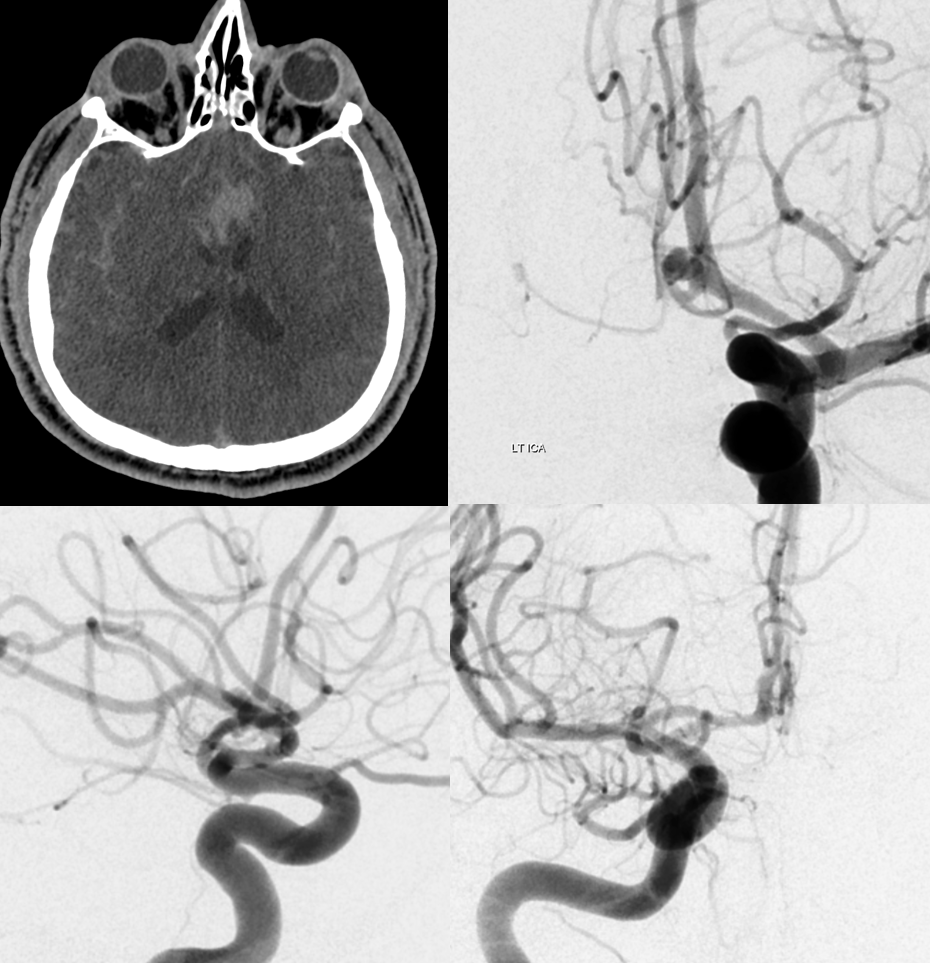

Great case by Vera Sharashidze and Sitara Koneru. Ruptured ACOM. Nothing much to see on 2D DSA — standard issue acom aneurysm, projects posterior…

Volume rendered stereo images of 10 second “micro” FOV 22 dyna Siemens Q — natural fill reconstruction, 3 cc/sec for 33 sec injection. Already better quality than most 3D-DSAs out there

Now we see a subcallosal artery from proximal A2.

Done? of course not. Secondary “small volume” reconstruction. Look at the two hypothalamic perforators — one from acom (dashed arrows), one from aneurysm neck (arrows). Both extremely important, all must be preserved for the sake of hypothalamic function…